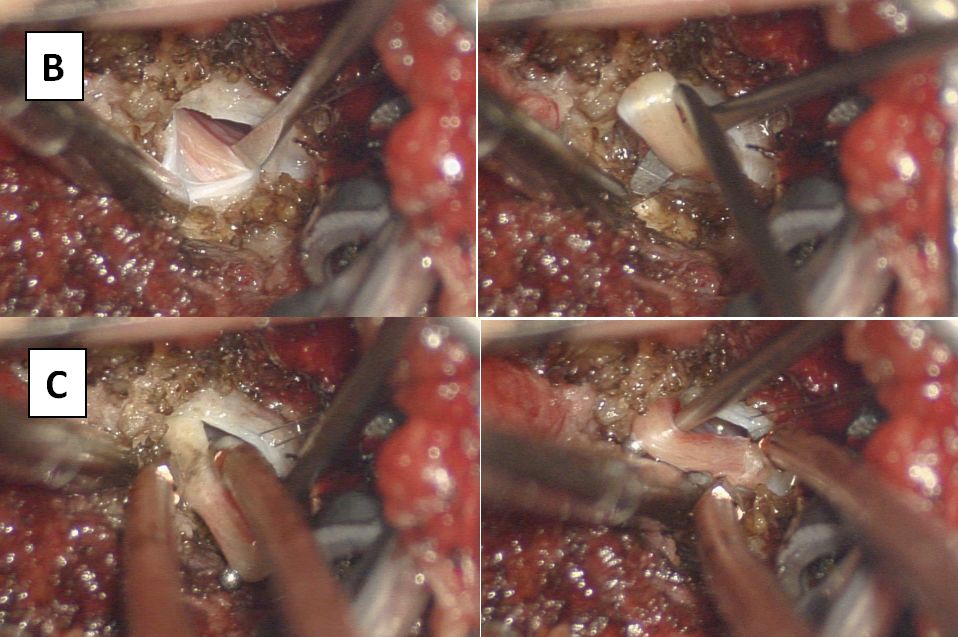

再次入院后予完善相关检查,相关病毒检测均提示阴性,炎症指标不明显。请神经外科会诊:结合患儿有下肢乏力,行走不稳,腰背部及双下肢疼痛,小便困难,大便失禁及便秘等症状,需排除存在脊髓栓系可能。回顾阅片初次的腰骶髓MR(图1):可见膀胱充盈扩张明显,横断面似见终丝脂肪浸润,建议再次复查MRI,可见终丝脂肪信号(图3)。

图3. 腰骶髓MR:箭头所指处可见终丝脂肪信号,T1上高信号,T2上低信号。

请放射科等多学科MDT讨论后认为:脊髓圆锥末端位于L1下缘水平,腰膨大形态较僵,终丝处于绷紧状态,位置偏后,横断面T2上终丝信号偏低,脂肪浸润可能,需考虑脊髓栓系综合征。